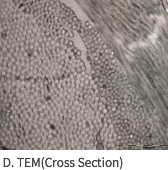

SEM Image (E-Beam 멸균 후에도 Collagen Structure를 유지)

MegaDerm의 3차원 진피구조

Collagen 조직을 파괴하지않는 세계 최초의 ‘E-beam’멸균